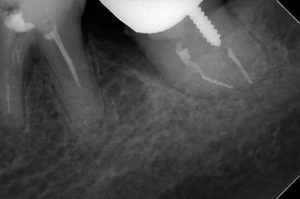

たとえば、下顎左側第二大臼歯の近心根に破折ファイルが認められます。

自発痛が強く、他院では抜歯してインプラントを勧められました。

当院で破折ファイルを除去したところ、とても喜んでくださいましたが、